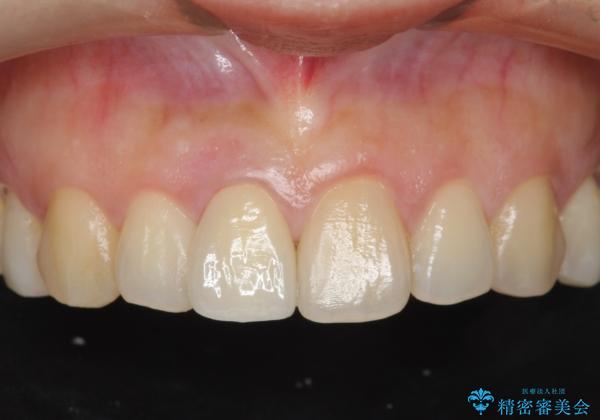

オーダーメイドで造る、自然な前歯セラミッククラウン

- 幼少期に前歯をぶつけて歯が折れ、神経の治療・クラウン治療を行った。グラつきと見た目の改善を希望して来院されました。

精密な仮歯をいれ、歯周組織を整えるとともにファイバーコア築盛、シェードテイキングを行い見た目に自然なジルコニアクラウンを製作していきます。

ジルコニアクラウンの中でも当法人のグレードの高い、スペシャル・エクセレントプランはオーダーメイドで色調を合わせることで周囲の歯に馴染んだ自然な歯を製作することのできるプランです。